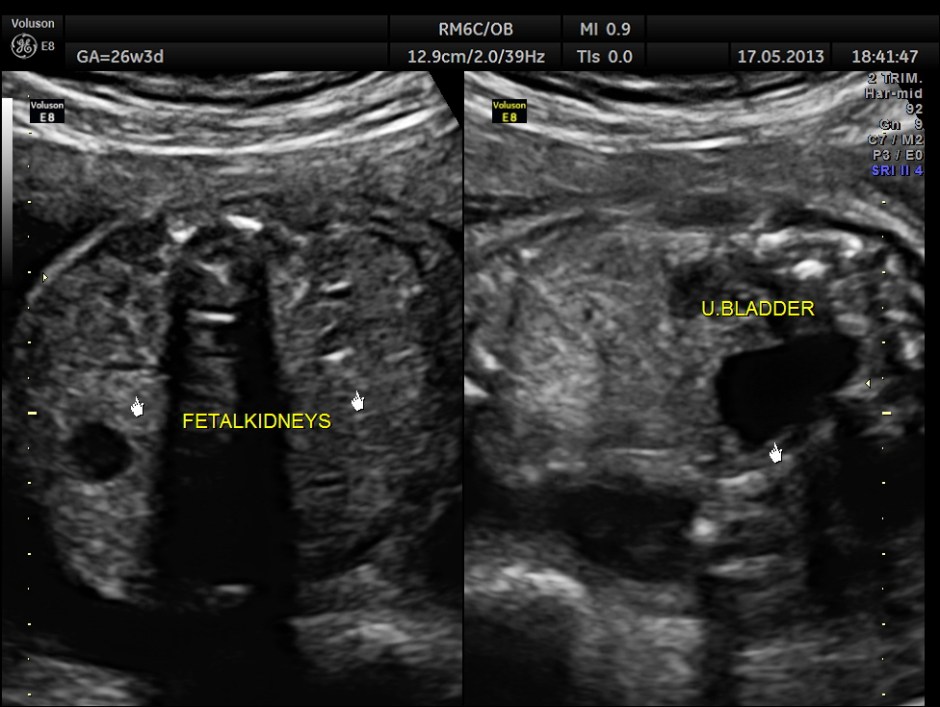

The abdominal images are given below.

This fetus did not show any oro-facial clefts ; heart and spine appeared normal.